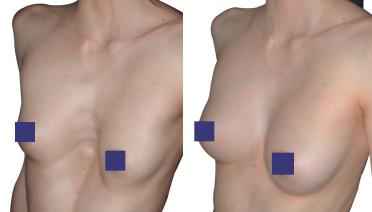

La tecnica di impianto su misura è una tecnica chirurgica minore che consiste nel riempire la concavità creata dal Pectus con un impianto personalizzato. Si tratta di un intervento rapido, a basso rischio, con un risultato immediato e una breve convalescenza.

In questa pagina, troverà i risultati di questa operazione a seconda del tipo di Pectus : mediale, asimmetrico, più o meno profondo o lungo.

Tipo 1 : Mediano, profondo e simmetrico,